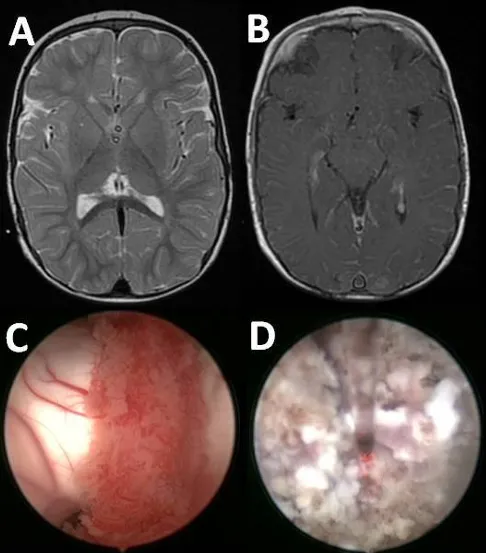

5周后,因新的分流功能障碍需要将两个脑脊液分流管都进行外置,这证实了脑脊液的每日过度产量约为1500毫升。尽管尝试使用特利加压素进行药物治疗,但效果不佳。因此,尽管磁共振成像显示脉络丛外观正常,还是进行了双侧内镜下脉络丛电凝术。由于脑室较小,该手术通过双侧枕部入路并在神经导航辅助下完成。自术后第一天起,脑脊液引流量减半至每日700-800毫升。尽管脑脊液产生率显著降低,但仍需维持双重分流。所幸术后过程平稳,患儿在6个月随访时状况良好。

图3.脑部磁共振成像(MRI)结果排除了影响脉络丛的病理状况(A)、(B)。脉络丛的内窥镜图像,包括使用前(C)及凝血操作期间(D)的情况。